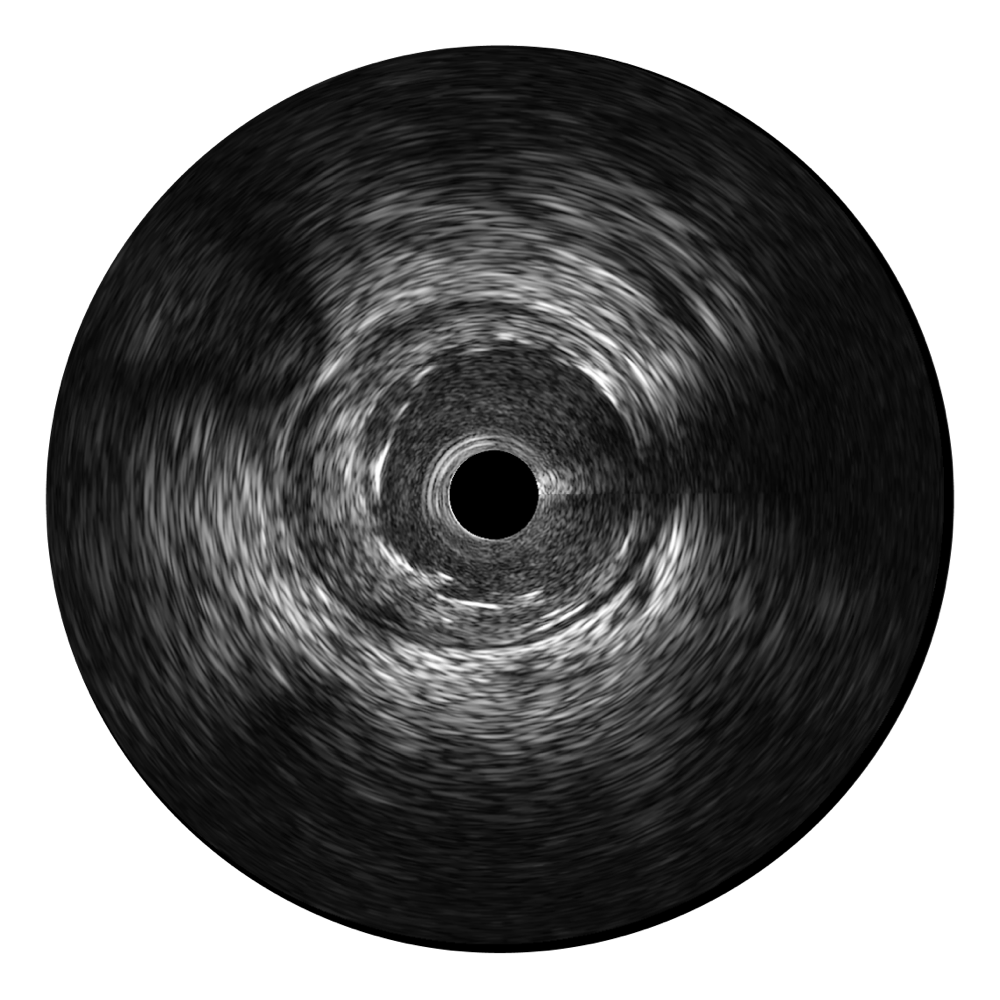

開立寬頻IVUS圖像

傳統(tǒng)IVUS圖像

對比傳統(tǒng)IVUS導管成像,開立寬頻IVUS圖像的近場支架梁顯影更細膩,遠場中膜外血管仍清晰可辨,兼顧遠中近,兼顧分辨力與穿透深度